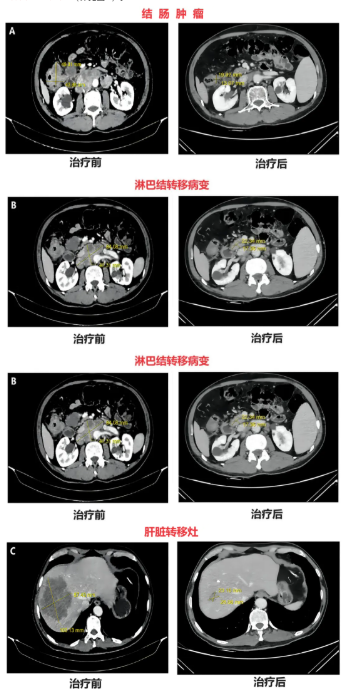

2、影像学检查结果:治疗前结肠镜检查显示距肛缘70cm处可见结节性菜花状病灶,病变肠道周围及上、中、下腹腔、腹膜后均有多发肿大淋巴结。结肠CT显示升结肠肝曲附近肠壁存在4.9cm×4.4cm肿块(详见图A),腹膜后淋巴结转移灶大小约8.4cm×4.7cm(详见图B)。肝脏CT可见肝内多发斑块状、结节状低密度影,其中肝右叶较大肿瘤约10.3cm×8.7cm(详见图C)。

▲图源“PMC”,版权归原作者所有,如无意中侵犯了知识产权,请联系我们删除

在第三次治疗后,CT显示各病灶明显缩小:结肠病灶缩小至2.0cm×1.3cm,肝脏病灶缩小至2.6cm×2.3cm,淋巴结病灶缩小至2.2cm×1.7cm(详见下表),部分病灶已在影像学上消失,达到部分缓解(PR),此时肿瘤大小已符合根治性手术条件。随后,患者接受肝转移灶微波消融(MWA),并针对结肠原发肿瘤及相关淋巴结行开放性根治性右半结肠切除术。最终,患者实现病理学完全缓解(pCR),且未出现严重副作用。